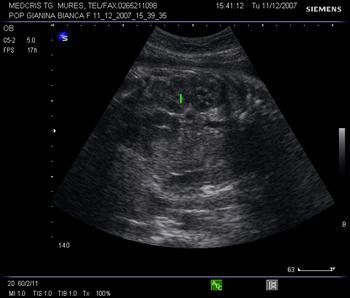

Fig . nr. 186. Sectiune transversala la nivel abdominal, cu stomacul anecogen si vena ombilicala ( sageata )